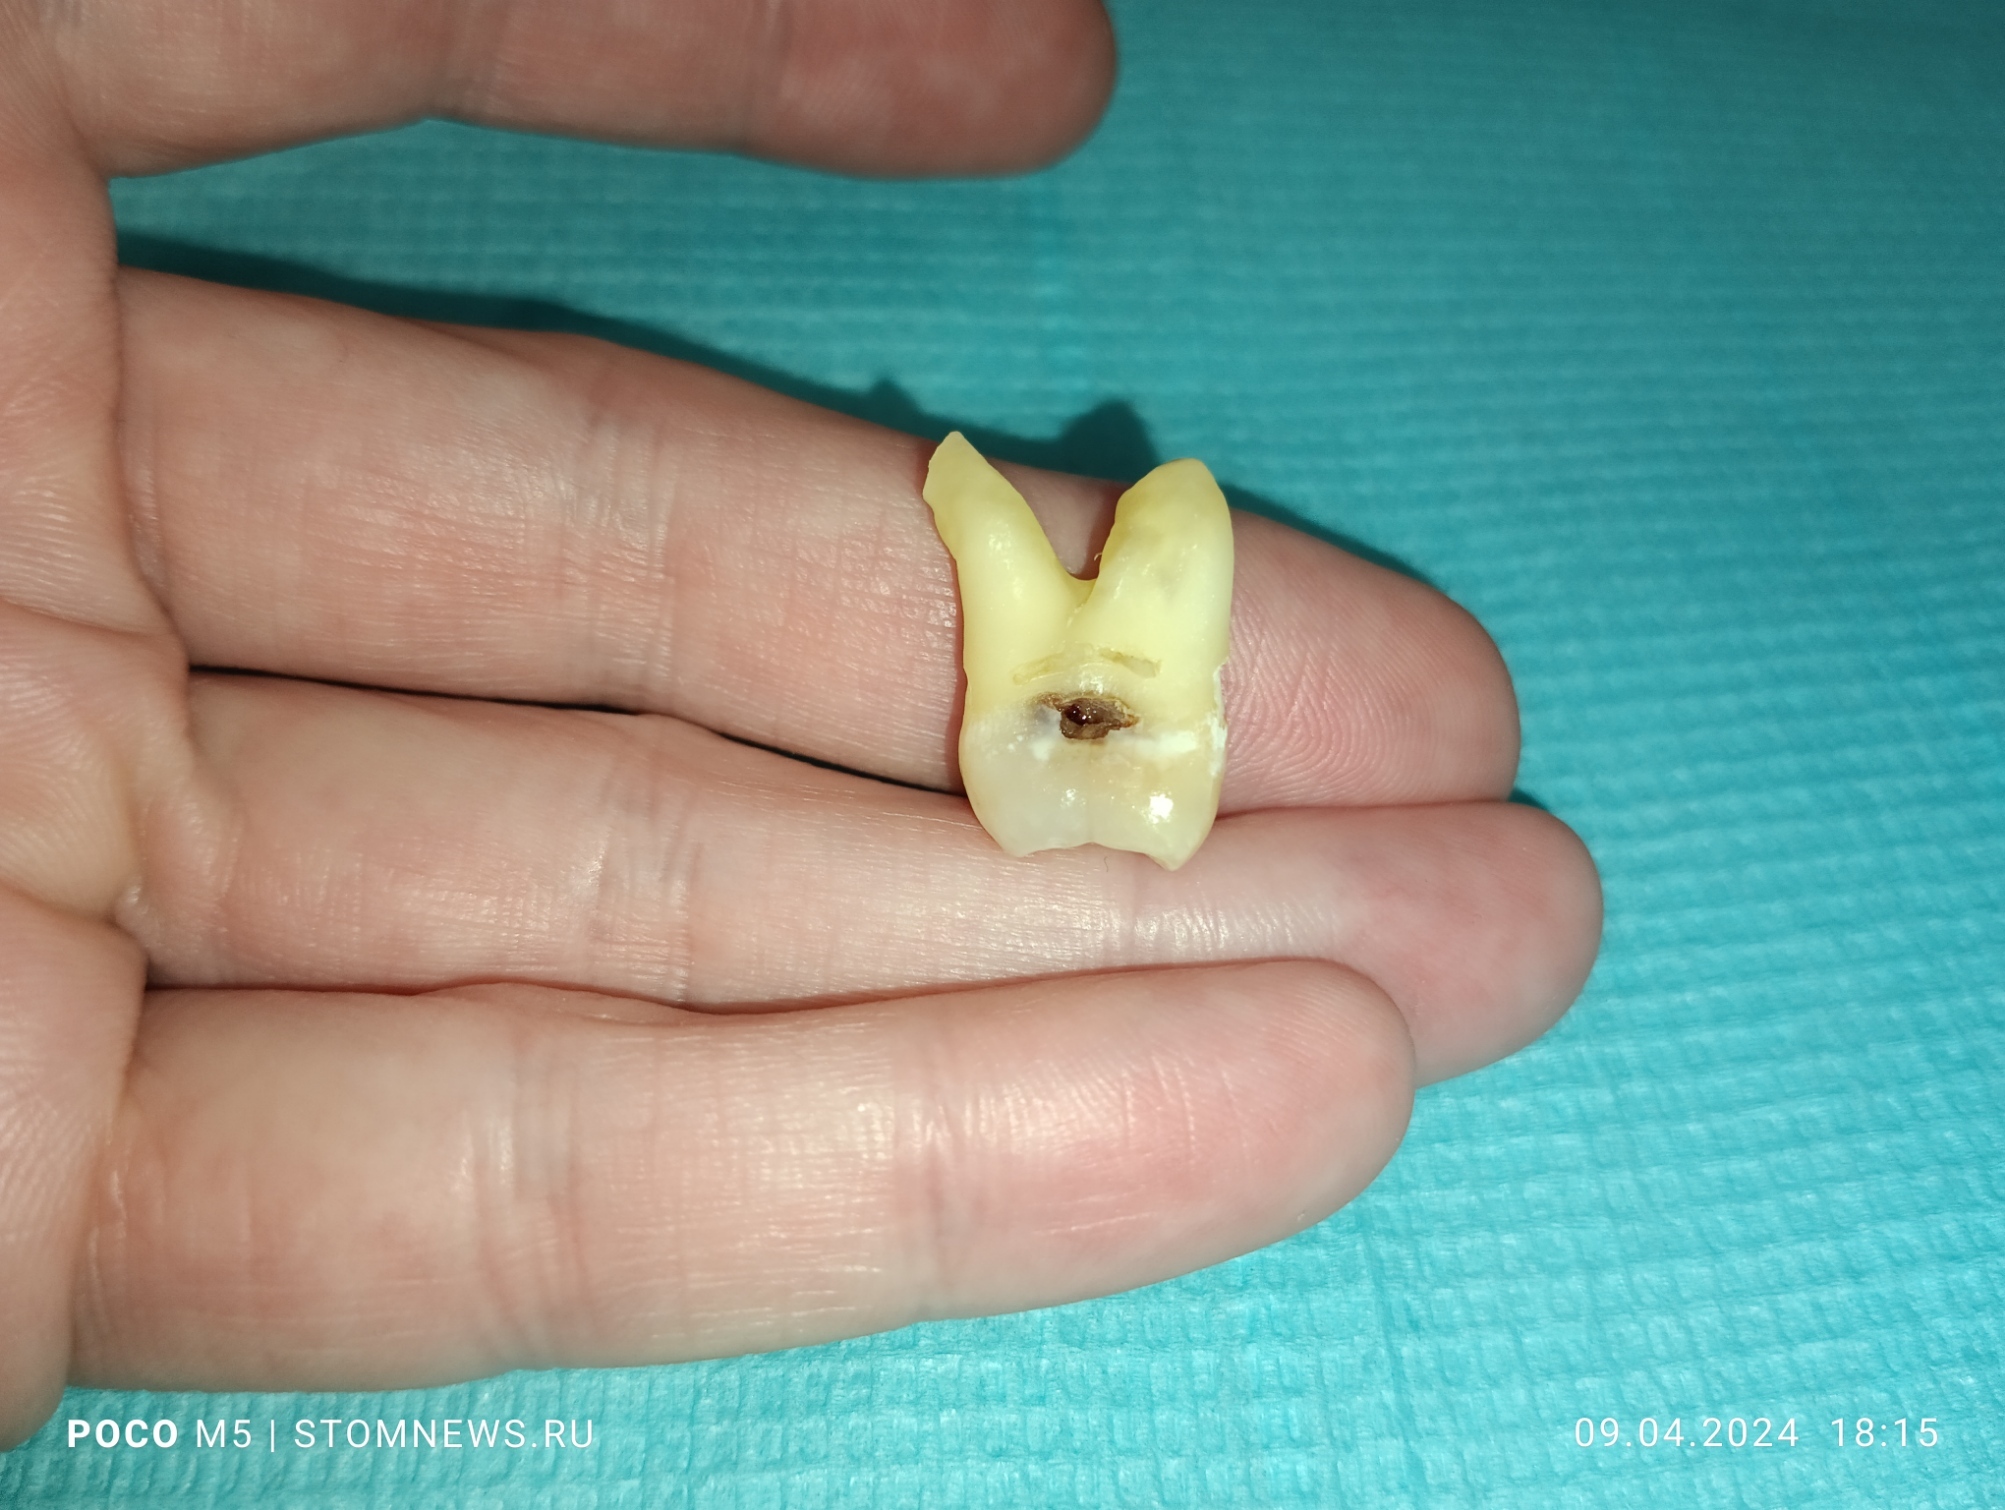

Удаленный 28 зуб мудрости с корнями по типу «оленьи рога»

💥Вот такой клинический случай произошел у меня на приеме сегодня: 09.04.20024 💥

😬Как оказалось, у пациента слева вверху запряталась восьмерка, которая только не давно прорезалась. При пальпации слизистой в области 28 зуба пациент резко дёргался 😱😱😱

☄️Было принято решение об удалении, так как спасти его не представлялось возможным👊

✌️Я решил сделать серию фотографий и выложил их на свой собственный сайт в виде галереи. Если вам интересно посмотреть поближе на этого монстра, то переходите по ссылке ниже👇👇👇